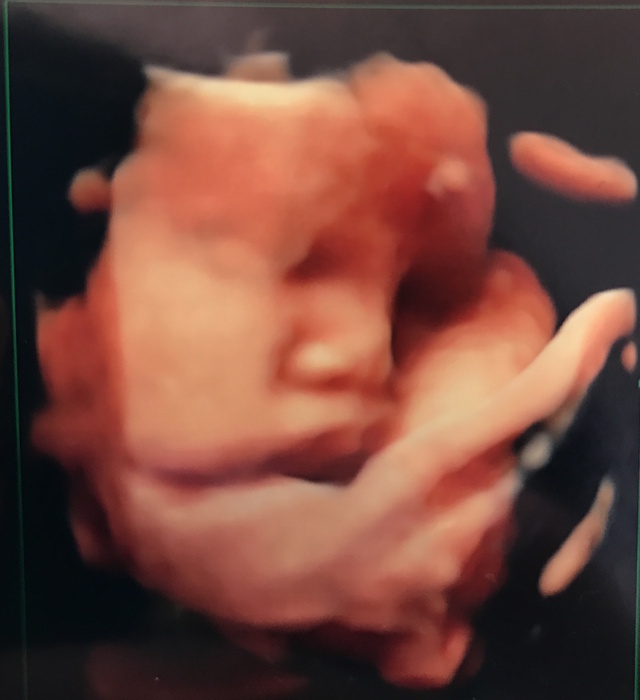

36週1日(36w1d・男の子)|トーママ さん(28歳)

エコー写真撮影時のエピソード:

標準よりも少し大きめに成長していた息子。 エコー写真をもらうたびに主人にラインで送ってました。

大体いつもよくわからんねとか言ってた主人ですが、この写真を送ると速攻返信が… 完全にあなたの血を引き継いでるねと。

自覚はしていませんが、私がアヒル口みたいで、それのことを言われました… 姉に送っても言われ、友達に送っても言われました。